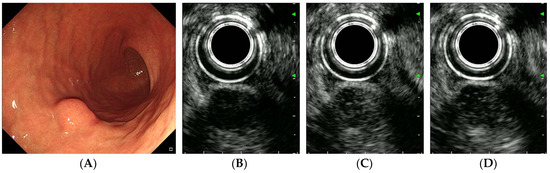

| CE-EUS findings | |||

| Arterial phase | |||

| Arterial enhancement | 0.024 | ||

| No/hypo-enhancement | 7 | 2 | |

| Iso/hyper-enhancement | 20 | 39 | |

| Irregular vessels | 0.017 | ||

| Absent | 21 | 20 | |

| Present | 6 | 21 | |

| Venous phase | |||

| Diffuse enhancement | 0.035 | ||

| Absent | 9 | 5 | |

| Present | 18 | 36 |